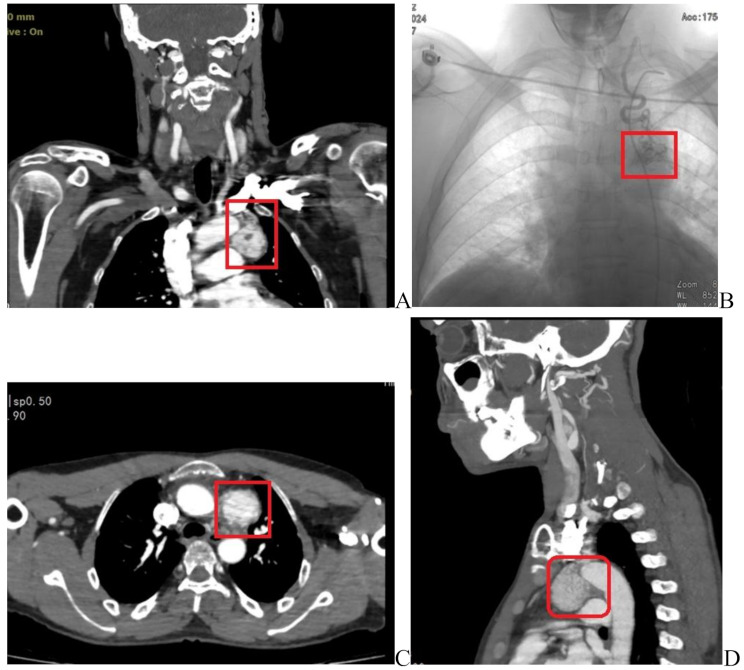

Case presentation: The patient was a 46-year-old male with a history of surgical removal of a mass from the right side of the neck, who presented with dysphonia lasting two months, hoarseness, vague chest pain, and unilateral ptosis. CT angiography of the carotid arteries and thoracic aorta revealed multiple findings, including a well-defined enhancing mass measuring 33 × 39 mm in the aorto-pulmonary prevascular space, a grade I carotid body tumor on the left side of the neck, vagal paragangliomas on the right side of the neck, and a glomus jugulare tumor on the right side. These findings were collectively suggestive of multiple paragangliomas. The patient subsequently underwent surgical resection of the mediastinal tumor, and pathological examination confirmed the diagnosis of paraganglioma.